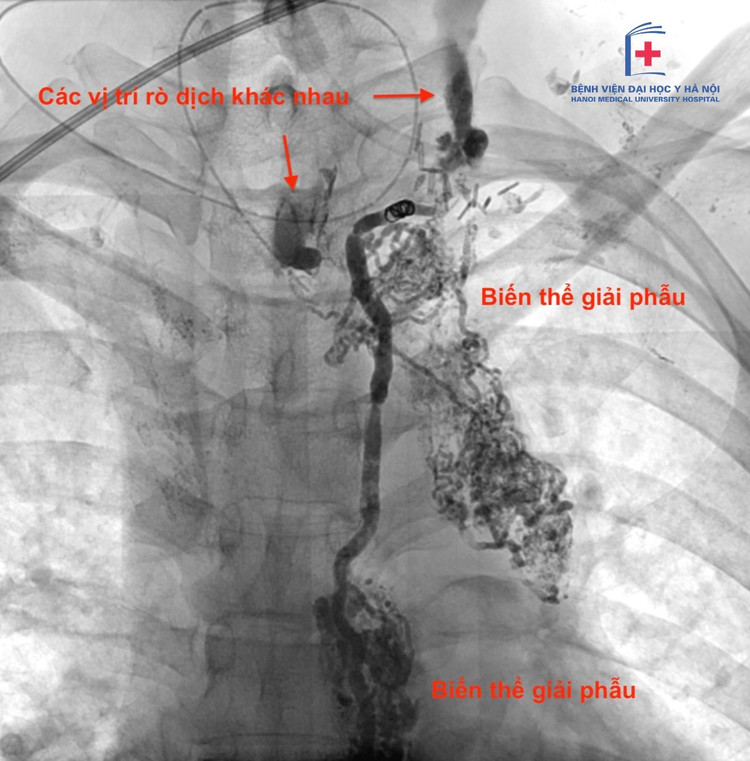

ro-duong-chap-1.jpg

Dịch rò dưỡng chấp trên phim chụp - Ảnh BVCC

Theo TS.BS Nguyễn Ngọc Cương, Trưởng khoa Can thiệp điện quang, Bệnh viện Đại học Y cho biết: Rò dưỡng chấp không hoàn toàn phản ánh kinh nghiệm phẫu thuật hay mức độ xâm lấn của khối u. Trong nhiều trường hợp, nguyên nhân xuất phát từ biến thể giải phẫu vốn có của người bệnh.

Ở trường hợp kể trên, bệnh nhân có cấu trúc ống ngực với nhiều nhánh bàng hệ nhỏ tại vùng cổ. Chỉ cần tổn thương một vài nhánh li ti trong quá trình phẫu thuật cũng có thể dẫn đến rò dưỡng chấp, dù thao tác kỹ thuật vẫn được thực hiện đúng chuẩn.